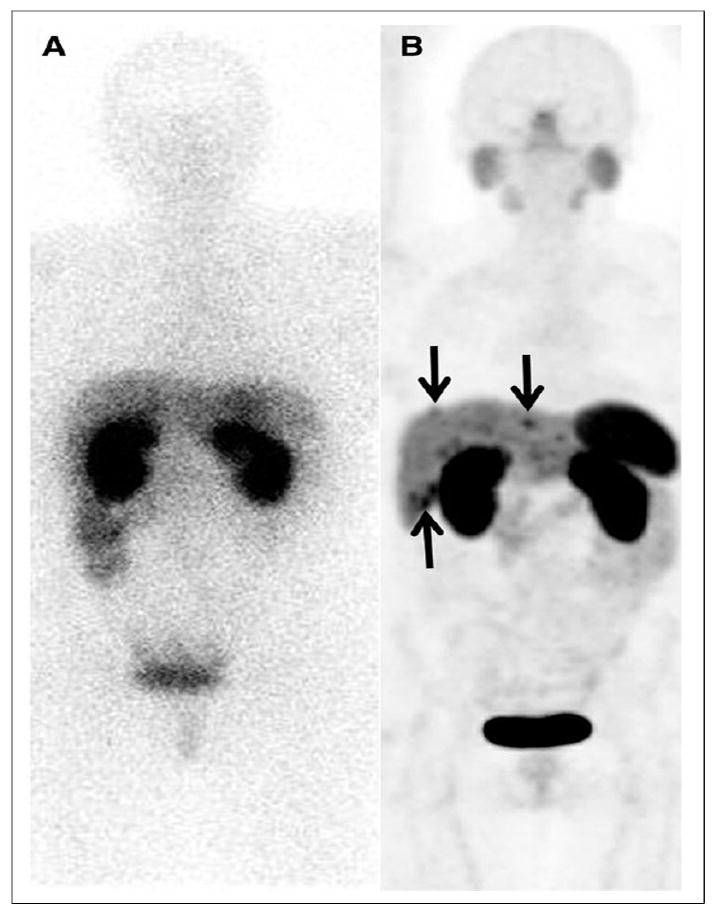

Actinium-225 treatment, before and after

Scans of tumor presence over treatment of metastatic prostate cancer with Ac-225. Source: J. Nuc. Med., v57, 2016, pp 1941-1944.